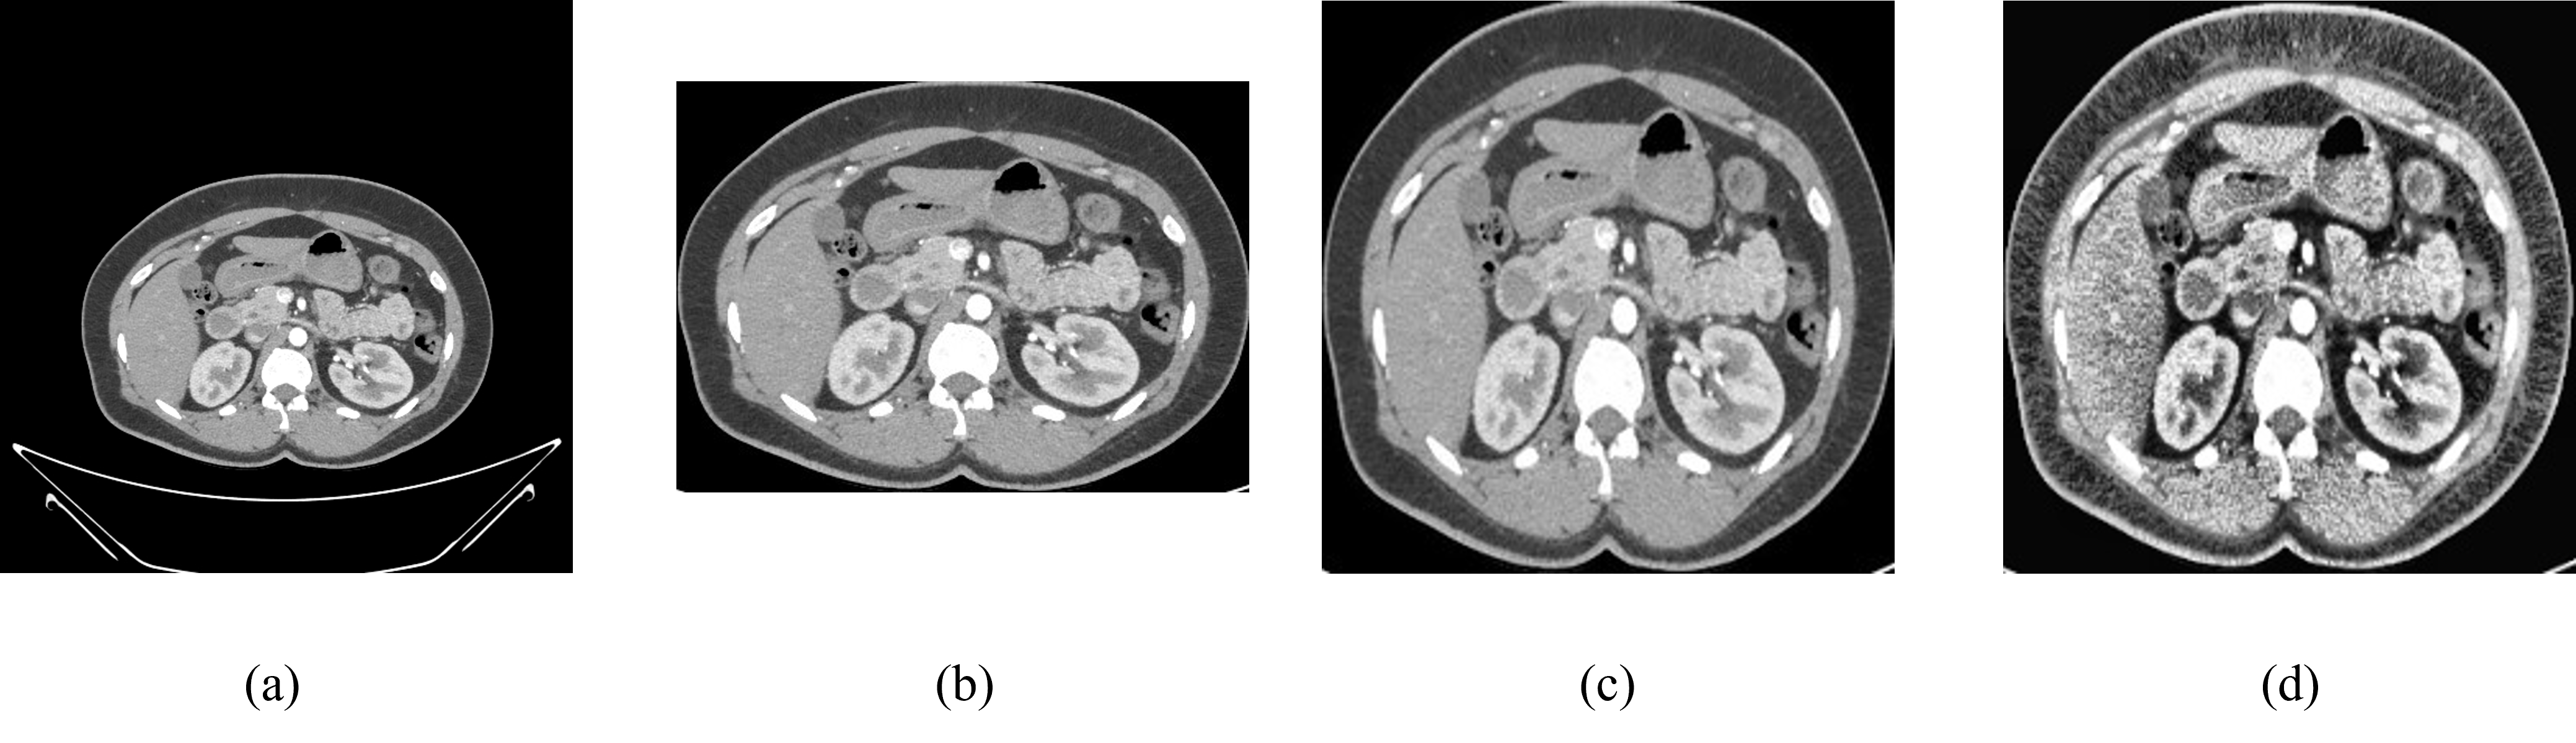

The initial phase of our image processing workflow involves meticulously cropping the CT scan images to isolate and emphasize the pertinent anatomical structures. This cropping process serves a dual purpose: first, it effectively eliminates extraneous background noise and non-essential elements from the images, thus enhancing the clarity and focus on the regions of interest. Second, it ensures that subsequent analyses are conducted with precision and efficiency, as they are directed toward the critical anatomical features essential for diagnosis and evaluation. Figure 3(a) is a raw dataset after that it has been cropped as shown in figure 3(b).

Following the cropping stage, we proceed to standardize the resolution of the images to a uniform size, typically resizing them into a standardized dimension of 224x224 pixels. This standardization is crucial for several reasons. Firstly, it facilitates consistency across the dataset, ensuring that all images are represented in a comparable format, which is essential for reliable and accurate analysis. Standardizing the resolution also helps to streamline subsequent computational processes, as it reduces variability and simplifies the integration of various image processing techniques and algorithms. Figure 3 (c) is an image after resizing it into 224x224 pixels.

5.1.2 Apply Contrast-Limited Adaptive Histogram Equalization (CLAHE) to the Data

CALHE, or Contrast Adaptive Local Histogram Equalization, is an innovative technique that enhances image contrast by adjusting to local intensity variations, unlike traditional global histogram equalization methods. By considering the local context, CALHE proves particularly valuable for identifying subtle anatomical structures and anomalies in medical images. Its adaptive approach revolutionizes visualization, offering unprecedented precision and detail, thus advancing both research and clinical practice in radiology and beyond. Figure 3 (d) is an image after applying CLAHE which enhances the image more than regular raw data.

Refer to caption

Figure 3: (a) Raw Normal Kidney Image (b) Cropped Image (c) Resized Image (d) CLAHE Applied Image